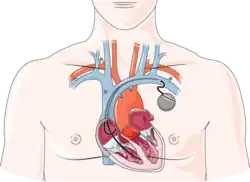

Based on the benefits summarized below, CR programs are recommended by the American Heart Association / American College of Cardiology[5] and the European Society of Cardiology,[6] among other associations.[7][8] Patients typically enter CR in the weeks following an acute coronary event such as a myocardial infarction (heart attack), with a diagnosis of heart failure, or following percutaneous coronary intervention (such as coronary stent placement), coronary artery bypass surgery, a valve procedure, or insertion of a rhythm device (e.g., pacemaker, implantable cardioverter defibrillator).[9] However, some populations, including women[10][11] and older patients[12], are less likely than others to seek out and complete these types of programs.